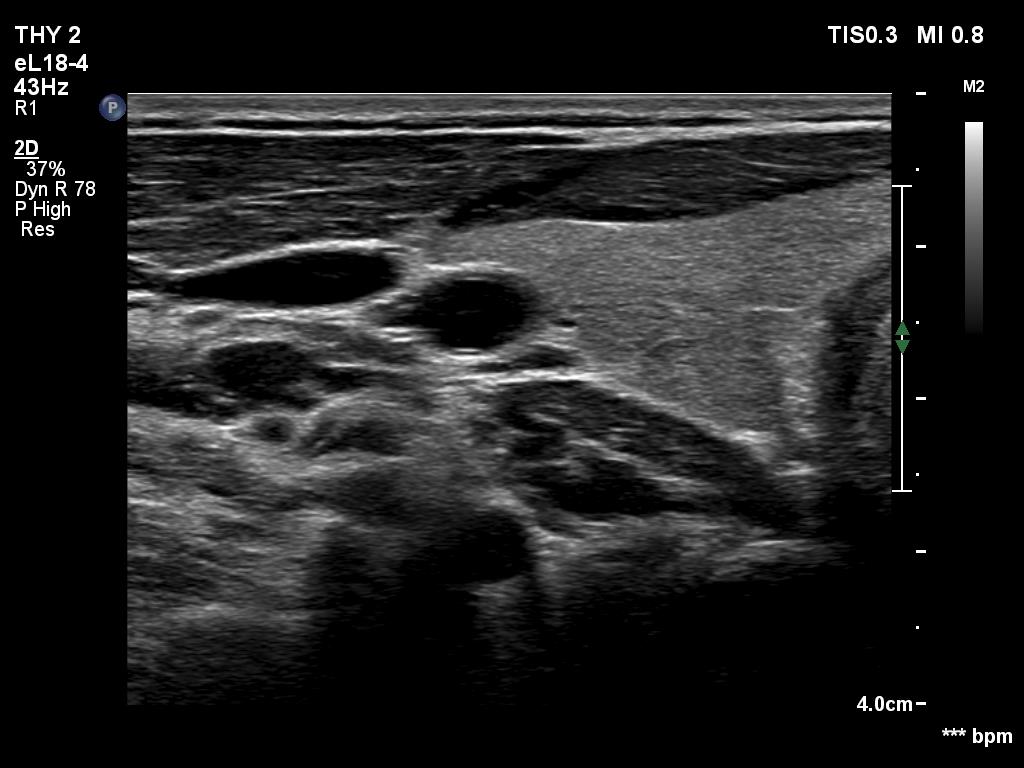

Ultrasonography. The thyroid was echonormal. There was a discrete, minimally hypoechoic area in the dorsal part of the right lobe. This was a technical artifact, caused by a connective tissue band crossing the thyroid. Although on transverse scan, the lesion looked deceptively as a discrete lesion, the real situation became clear on longitudinal scan.